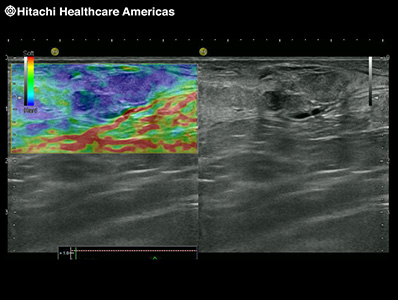

An innovative diagnostic tool that provides real-time color display of tissue elasticity.